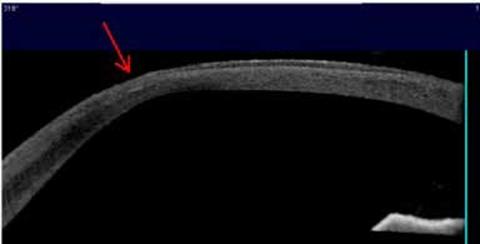

iv.   Buttonhole κρημνός

Η αποτυχία επίτευξης κοπής στο κέντρο έχει ως αποτέλεσμα μια τρύπα στον κρημνό (Εικόνα 4b,5). Παρατηρείται στο 0,03% έως 2,6% των περιπτώσεων51. Ο κυρτός κερατοειδής (>48D), η απώλεια αναρρόφησης, ο μεγάλος κρημνός, το δεύτερο μάτι, το m-LASIK και το vertical gas breakthrough (VGB) στο FS-LASIK αποτελούν παράγοντες κινδύνου51,52. Η διαχείριση περιλαμβάνει ματαίωση της διαδικασίας και σχεδιασμό μιας εκ νέου θεραπείας, κατά προτίμηση με επιφανειακή φωτοεκτομή μετά από τρεις μήνες. Σε περίπτωση που επιχειρηθεί εκ νέου LASIK θα πρέπει να γίνει κρημνός μεγαλύτερης διαμέτρου και μεγαλύτερου πάχους39. Η δημιουργία buttonhole κρημνού μπορεί να οδηγήσει σε ανώμαλο αστιγματισμό και μετανάστευση επιθηλίου.